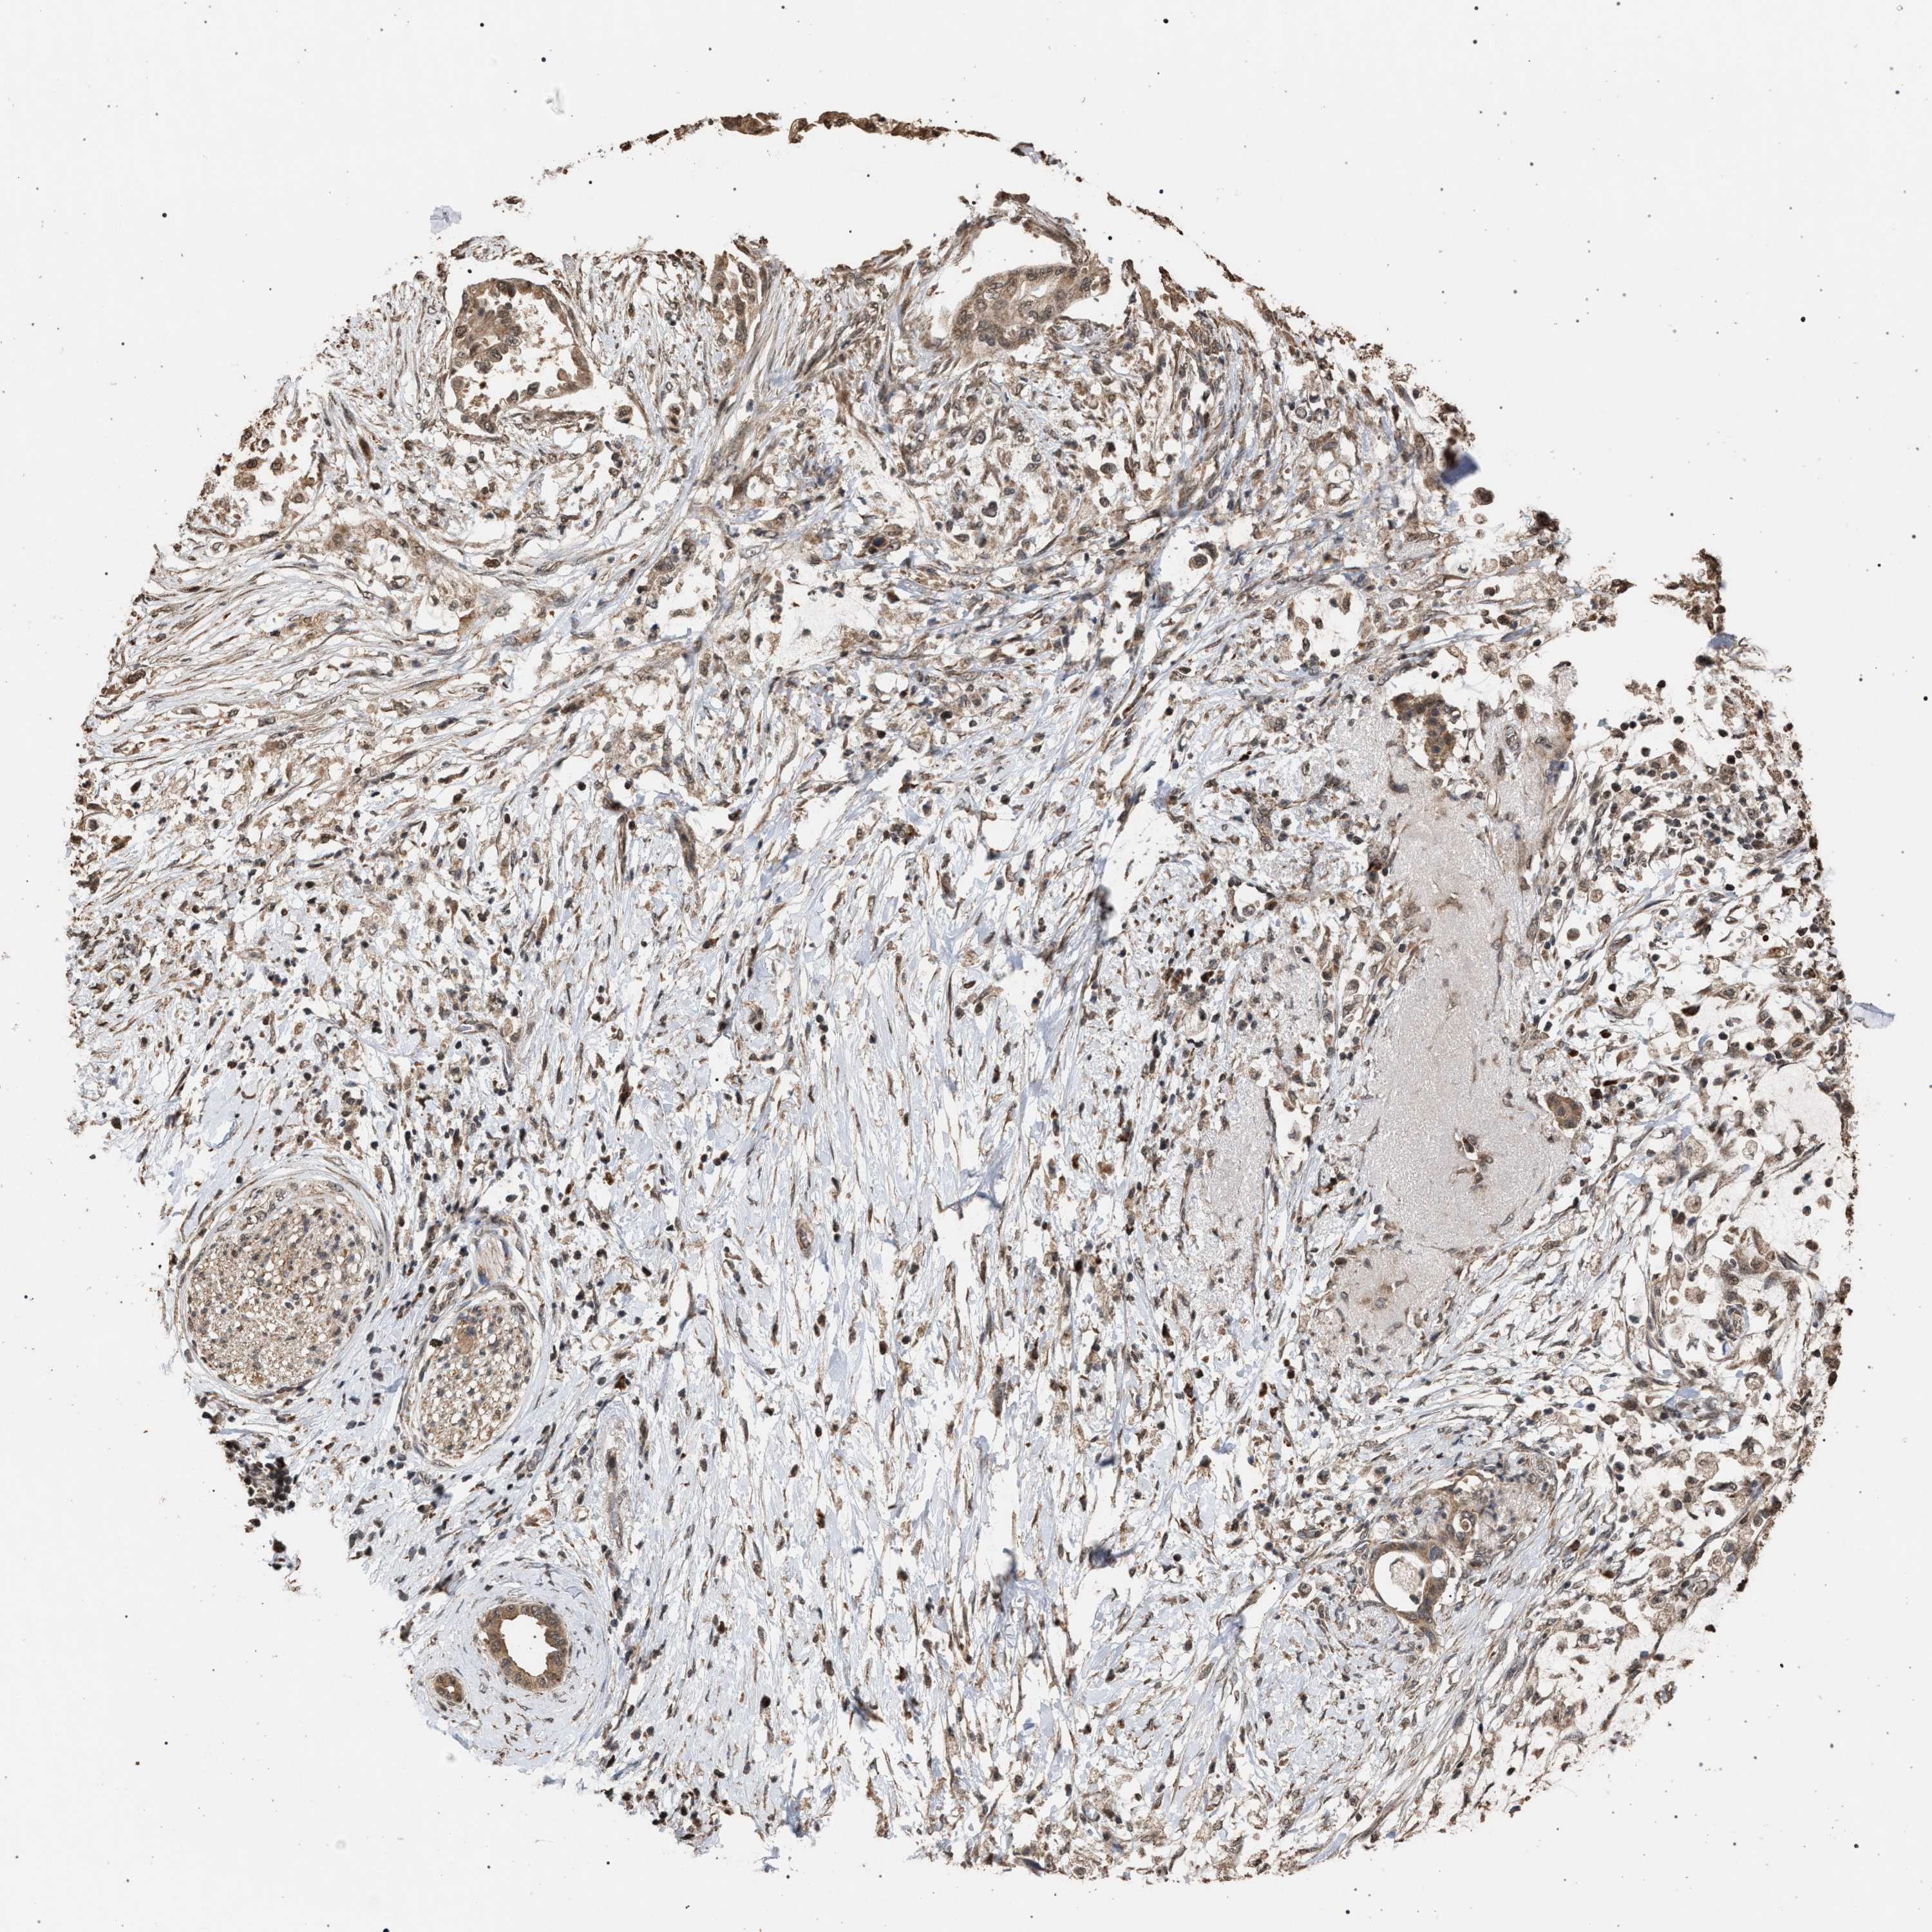

PANCREATIC CANCER - Protein expressioni

A mouse-over function shows sample information and annotation data. Click on an image to view it in a full screen mode. Samples can be filtered based on level of antibody staining by selecting one or several of the following categories: high, medium, low and not detected. The assay and annotation is described here.

Note that samples used for immunohistochemistry by the Human Protein Atlas do not correspond to samples in the TCGA dataset.

Antibody stainingi

Antibody staining in the annotated cell types in the current human tissue is reported as not detected, low, medium, or high, based on conventional immunohistochemistry profiling in selected tissues. This score is based on the combination of the staining intensity and fraction of stained cells.

Each image is clickable and will lead to virtual microscopy that enables deeper exploration of all samples and also displays staining intensity scores, fraction scores and subcellular localization as well as patient and tissue information for each sample.

Antibody HPA021547

Staining

High

Medium

Low

Not detected

Intensity

Strong

Moderate

Weak

Negative

Quantity

>75%

75%-25%

<25%

None

Location

Nuclear

Cytoplasmic/membranous

Cytoplasmic/membranous,nuclear

Adenocarcinoma, NOS